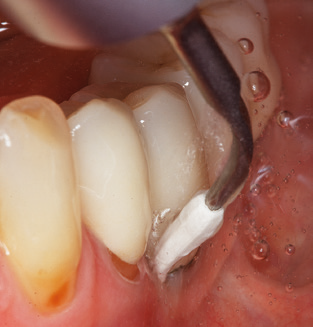

Dopo la pulizia meccanica delle superfici dei denti e degli impianti, le superfici dei denti naturali vengono pulite manualmente utilizzando strumenti manuali standard. Quando si esegue la pulizia manuale, è necessario prestare particolare attenzione a mantenere il corretto angolo di applicazione, un'adeguata nitidezza, un buon supporto e lavorare con la curette dall'apicale al coronale. Curette in titanio o carbonio devono essere utilizzate per la post-pulizia delle strutture dell'impianto (Fig. 8). Oltre all'uso di dispositivi ad ultrasuoni, i dispositivi power jet possono essere utilizzati anche in odontoiatria conservativa. Tuttavia, si deve considerare che queste procedure non sono adatte per rimuovere depositi duri e quindi non possono sostituire completamente l'uso di strumenti manuali e strumenti ad ultrasuoni. In tutti i casi, la pulizia è seguita dalla lucidatura meccanica del dente accessibile e delle superfici dell'impianto con ventose e composti di lucidatura (Fig. 9).